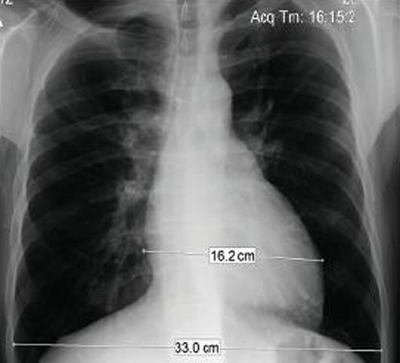

Ressonância nuclear magnética em um paciente com regurgitação pulmonar após reparo de tetralogia de Fallot. O paciente tem ventrículo direito não restritivo e o coração é grande

De: Chaturvedi RR, Redington AN. Heart. 2007 Jul;93(7):880-9; usado com permissão